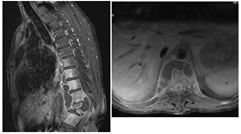

A: SAGITTAL T1W; B: SAGITTAL T2W; C: SAGITTAL T2W; DAXIAL T2W

Figure 6: 33 yr old male presenting with back pain with tingling and Numbness in both lower limbs. Collapse of the L1 and L2 vertebral bodies (A,B,C) seen with adjacent paraspinal and B/L psoas abscesses (D). The debri is seen causing spinal stenosis and cauda equina compression.